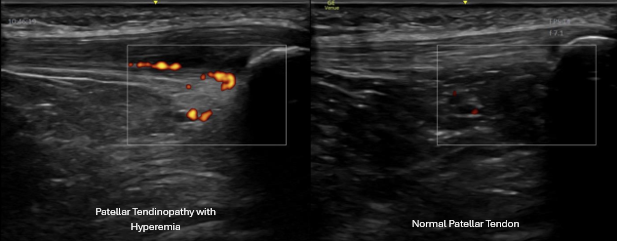

Dynamic knee ultrasound exam comparing injured and non-injured tendon tissue

Tendon pathology

• Patellar tendinopathy

• Chronic degenerative tendon changes

Ultrasound allows us to visualize the tendon and surrounding structures, perform dynamic exams, and compare findings to the opposite side when needed.